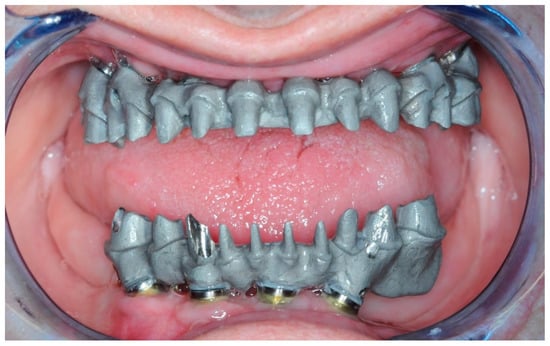

2.4. Temporary Prosthesis